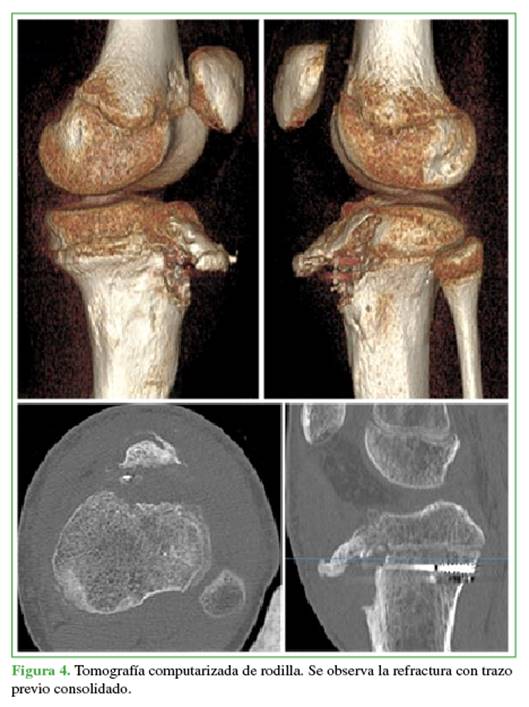

A los 4 meses, acudió nuevamente por dolor e impotencia funcional en la rodilla izquierda tras una hiperextensión. Tenía derrame articular, rótula ascendida y dolor en la TTA. En la radiografía, se observaba una fractura-arrancamiento de la TTA tipo IIB de Ogden. En una tomografía computarizada, se descartó el compromiso intrarticular y se confirmó la consolidación del trazo posterior de la fractura inicial (Figuras 3 y 4).